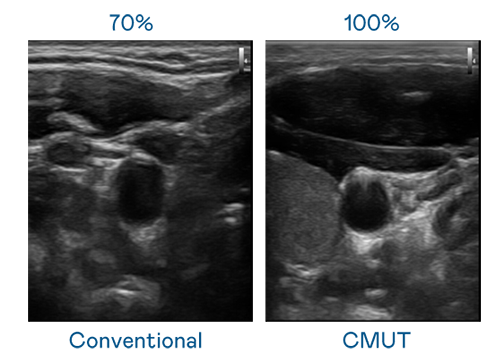

CMUT 技术是一种用电容式微机电元件来产生超音波讯号的技术。与传统 PZT 压电式技术相比,CMUT 频宽增加 30%,更宽频的超音波讯号让影像解析度大幅提升,是实现高影像品质医疗超音波扫描、促进精准医疗发展的关键技术。

大频宽带来超清晰影像

超音波影像的解析度高低,首先取决于探头能发出的讯号频宽。龙八国际 CMUT 可提供高清晰的超音波讯号,提供高频宽、高灵敏度、影像纹理细节更高的超音波影像,协助医护人员缩短影像判读时间及利用精准的医疗影像进行诊断。